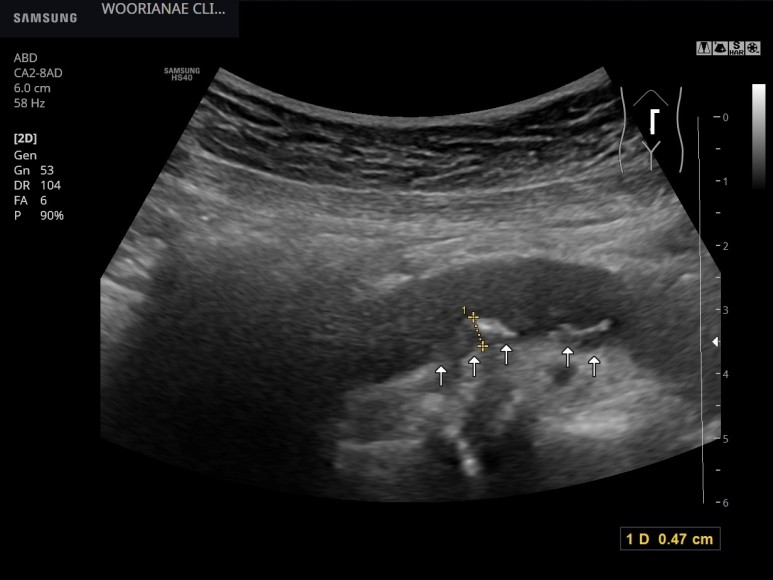

플라크(plaques) 소견 – 동대문구 답십리, 우리안애내과 흡연여성에서 복통평가 중 발견된 복부대동맥의 동맥경화,

복부초음파 시행췌장 등의 고형장기는 대부분 잘 관찰되었으며 종양성 병변은 관찰되지 않았다.

대동맥의 뺨이 쑤시는 등 배제를 위해 혈관도 관찰하지만…명백한 동맥경화, 플라크가 관찰된다; 20대 때부터 흡연력

사슴벌레 모양의 확장 소견(aneu rysmalchange)은 없었고 동맥 주변에 저음영 이상 소견은 관찰되지 않았다.